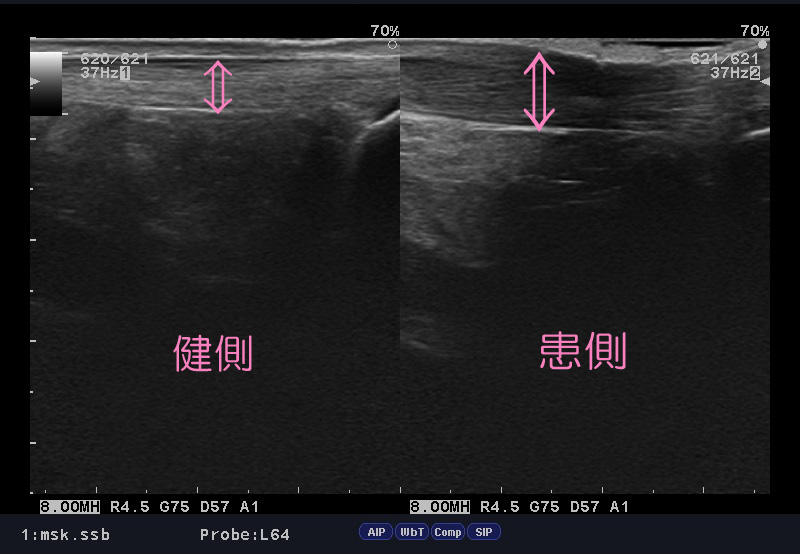

ふくらはぎの肉離れ

西武新宿線 東伏見駅南口『まる接骨院』です。 ここ数日、気温の低下からか、「肉離...